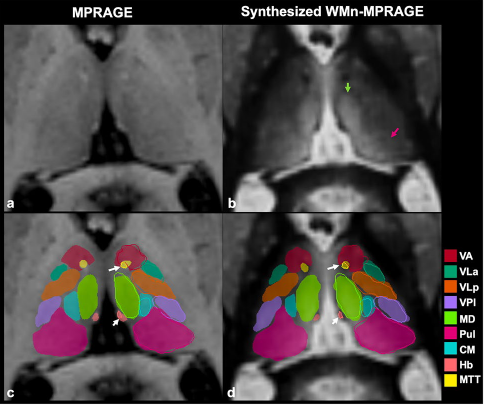

Visualization of thalamic nuclei

Thalamic nuclei are almost invisible on standard T1 and T2 MRI. We have been pioneering novel methods for visualizing thalamic nuclei.  These are critical for many applications like deep brain stimulation (DBS) electrode placement and focused ultrasound ablation of thalamic nuclei for treatment of essential tremor. They are also important to study atrophy of these nuclei in various neurodegenerative and neuro-psychiatric disorders. We have developed and optimized a novel white-matter-nulled (WMn) MRI sequence which enables clearer delineation of thalamic nuclei (top left, top centre) compared to conventional T1 MP-RAGE sequence (bottom left, bottom centre). Manual segmentation of some thalamic nuclei and the Morel atlas are shown in the far right column.

Fast automated segmentation of thalamic nuclei

THalamus Optimized Multi Atlas Segmentation (THOMAS) is a state of the art method we have developed for segmentation of WMn MRI data. It uses 20 prior manually segmented data sets for segmentation of new input data. We have also adapted THOMAS to segment the more readily available T1 MRI data, albeit with some reduction in accuracy. THOMAS has also been modified to create an atlas in MNI space which has been incorporated into leaddbs, a very popular open source software for DBS lead placement in neurosurgery.

More recently, we have been exploring sophisticated deep-learning methods to improve accuracy and speed of thalamic nuclear segmentation. One method synthesizes WMn MRI data from standard T1 MRI data and segments it using convolutional neural networks (CNN), opening the door for rapid analysis of databases such as ADNI, OASIS, and HCP. We have also developed a simpler more robust version using polynomial synthesis.